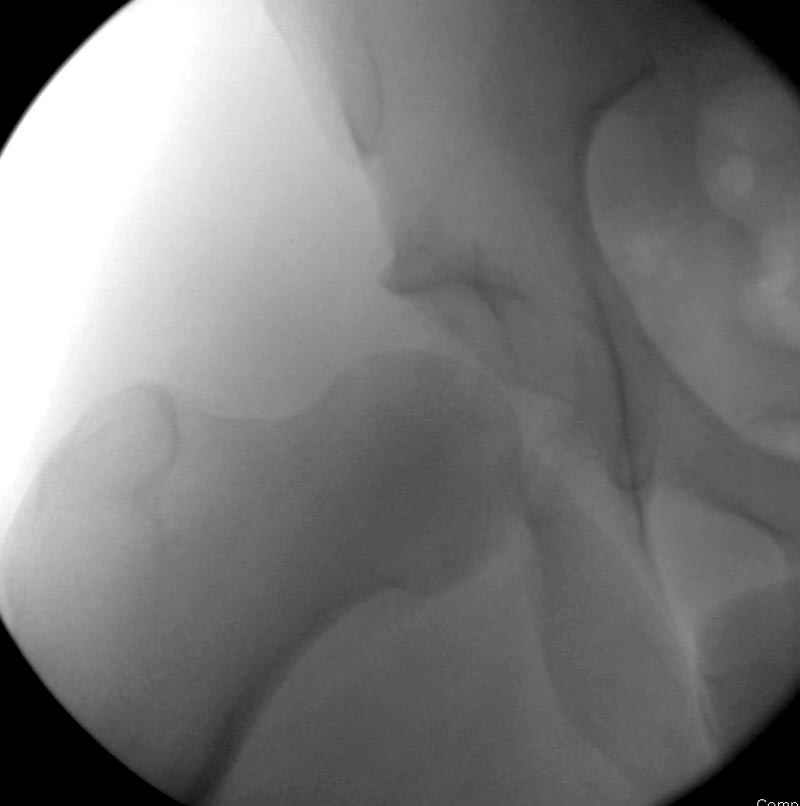

Интраоперционные N5 косая запирательная и N6 подвздошный снимок

11:50 больной в послеоперационной, рентгенограмма N7, компьютерная томограмма в тот же день N8-10